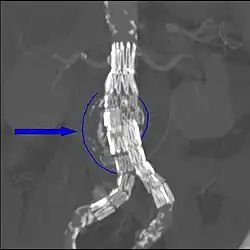

Diagnostic angiography images are captured of the aorta to determine the location of the patient's renal arteries, so the stent-graft can be deployed without blocking these. Failure to achieve this will cause kidney failure. With most devices, the "main body" of the endograft is placed first, followed by the "limbs" which join the main body and extend to the iliac arteries, effectively protecting the aneurysm sac from blood pressure.

The endograft acts as an artificial lumen for blood to flow through, protecting the surrounding aneurysm sac. This reduces the pressure in the aneurysm, which itself will usually thrombose and shrink in size over time.[14]